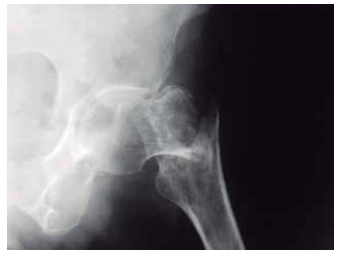

Observe a imagem a seguir:

A imagem contempla a região coxofemural, realizada em posicionamento anteroposterior, e refere-se a um(a)